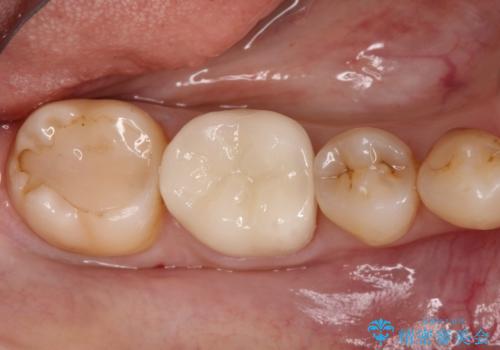

【オールセラミッククラウン】存在感のある銀歯を外したい

- 他院で矯正終了後、保定観察中の患者様が銀歯を白くしたいという主訴で来院されました。

オールセラミッククラウン(st)にて治療を行なっております。

オールセラミッククラウン(st)は

ジルコニアフレームに色調の再現がしやすいポーセレンを焼き付けた構造の被せ物です。